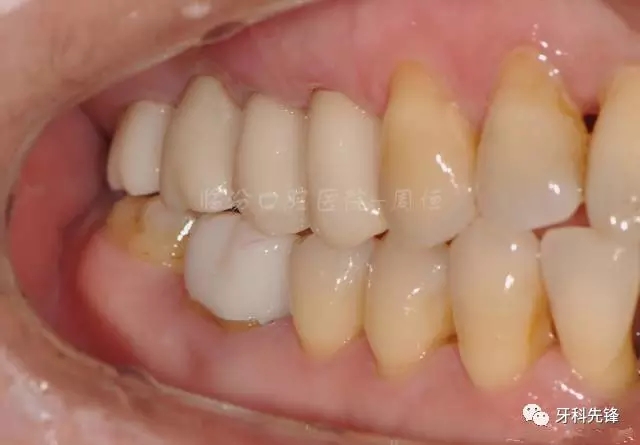

圖22烤瓷冠咬頜照

640.webp (26).jpg